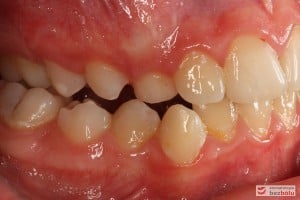

Rodzice zgłosili się z pacjentem celem rutynowej kontroli ortodontycznej. Wykonano OPG i po analizie modeli diagnostycznych stwierdzono brak miejsca dla wyrzynania dolnej prawej piątki stałej oraz zwężenie szczęki wraz z rotacją górnych zębów szóstych. W łuku górnym w pierwszym etapie leczenia zastosowano Rotator, celem odrotowania 6-tek stałych oraz ekspansji łuku w wymiarze poprzecznym. Następnie zamontowano aparat stały metalowy do uszeregowania zębów w łuku. W łuku dolnym miejsce odtwarzano stosując aparat stały i odpowiednią mechanikę leczenia. Leczenie aktywne trwało 3,5 roku, po czym zastosowano terapię retencyjną (retainer stały w żuchwie oraz Płytkę Hawley’a w szczęce).